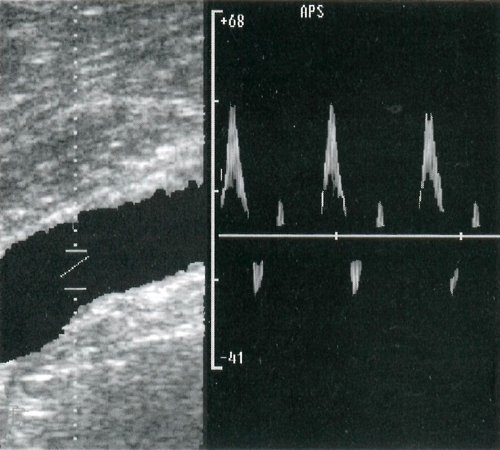

Рис. 2. Типы кровотока: а - магистральный, б - магистральный измененный, в - коллатеральный.

Магистральный тип - нормальный вариант кровотока в магистральных артериях конечностей. Он характеризуется наличием на допплерограмме трехфазной кривой, состоящей из двух антеградных и одного ретроградного пика. Первый пик кривой - систолический антеградный, высокоамплитудный, остроконечный. Второй пик - небольшой ретроградный (ток крови в диастолу до закрытия аортального клапана). Третий пик - небольшой антеградный (отражение крови от створок аортального клапана). Надо отметить, что магистральный тип кровотока может сохраняться и при гемодинамически незначимых стенозах магистральных артерий (рис. 2а, 4).

Магистральный измененный тип кровотока - регистрируется ниже места стеноза или неполной окклюзии. Первый систолический пик изменен, достаточной амплитуды, расширен, более пологий. Ретроградный пик может быть очень слабо выражен. Второй антеградный пик отсутствует (рис. 2б).

Коллатеральный тип кровотока также регистрируется ниже места окклюзии. Он проявляется близкой к монофазной кривой со значительным изменением систолического и отсутствием ретроградного и второго антеградного пиков (рис. 2в).